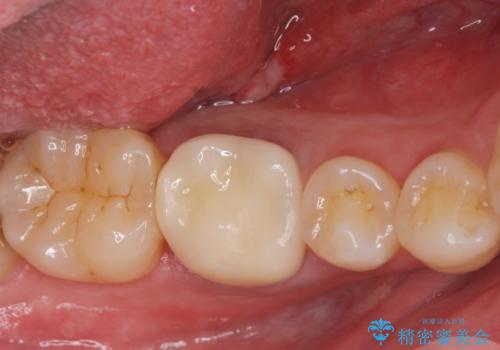

適合の良い被せ物が入りました。